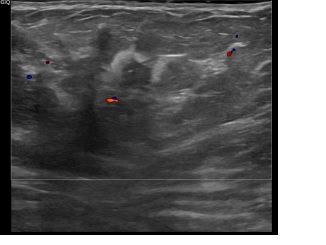

상기환자는  지속적인 유방통증으로 내원하신 30대초반

여성분으로 의심스러운 우측혹 조직검사 시행해 유방암 진단되었습니다